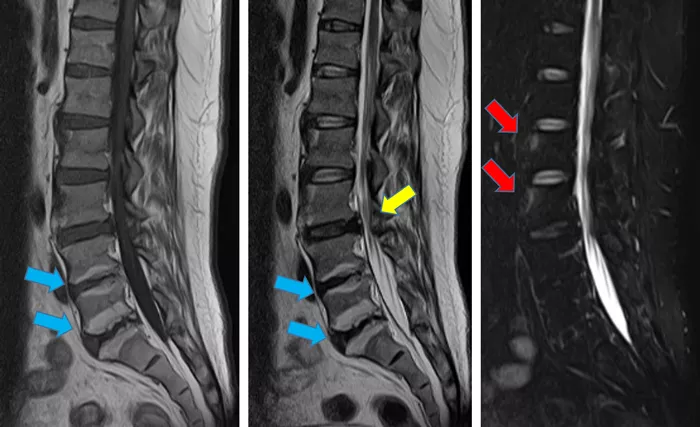

写真3

右仙腸関節斜位像では、関節裂隙の狭小化、骨硬化あり(赤矢印)。